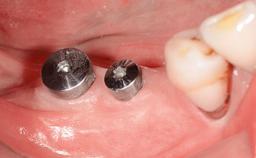

Maxillary Implant-supported Full-arch Removable Dental Prostheses for a Geriatric Patient: Sequencing the Treatment for an Optimal Outcome

A 90-year-old, essentially healthy woman requested assistance following what she determined was the loss of a dental restoration from a maxillary anterior tooth. She also complained of pain associated with tooth 11. The patient was assessed as relatively fit and healthy. She took medications for mild hypertension and to prevent angina attacks (atenolol and diltiazem). She had a form of arthritic joint degeneration affecting several joints; especially in her hands and fingers. When required she used an NSAID (meloxicam) for pain management. She reported living alone in a care facility that allows for independent living, with domestic support when and if necessary and primary medical triage when required.